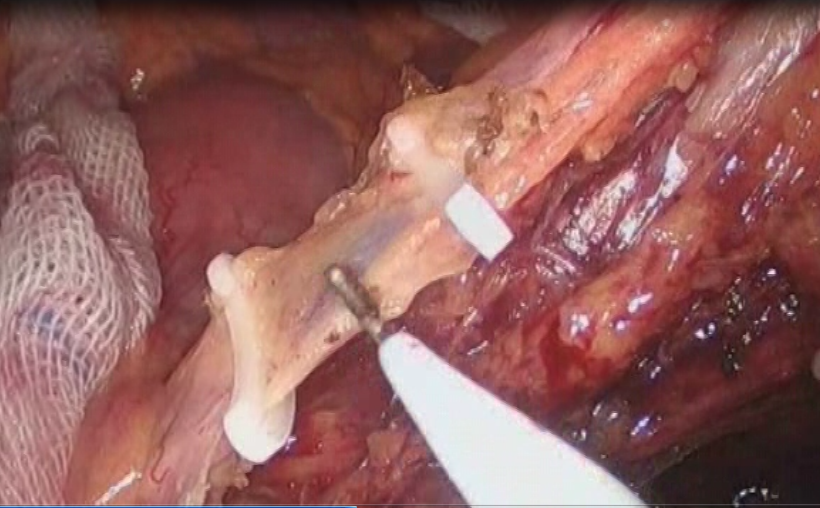

高龄直肠癌性梗阻处理的体会

结直肠癌是我国常见的恶性肿瘤,患者就诊时多已为晚期或局部晚期。由于肿瘤瘤体巨大,侵犯邻近脏器,多个脏器受累,临床处理有一定困难。部分外科医生面对晚期结直肠癌时选择放弃手术。但事实上,多学科综合治疗能使晚期或局部晚期患者获得相对好的治疗结果,不应该轻易放弃合理的外科手术。对于肿瘤巨大但没有远处转移,有多脏器受累的患者,直接手术切除困难,可以考虑进行术前的辅助治疗。外科手术原则是在能够达到R0切除的基础上,尽量保留脏器的功能,进行合理的区域淋巴结清扫。

这老太太87岁,肠癌梗阻,病情较晚,在其他医院不敢做,准备放弃了,来我院经过处理后,微创手术解决问题。